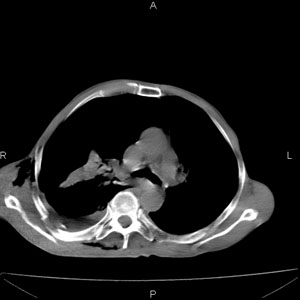

患者男,77岁,于3日前从树上摔下,头部查ct示蛛血,硬膜下出血,上腹部ct未见明显异常,右侧胸腔积液,左侧如常。肺部拍片示右侧肋骨多发骨折住院后今日来查肺部ct,我看到的是1。右侧胸腔血气胸并右肺上叶,中叶压缩性肺不张,2。右肺下叶肺挫伤并多发肋骨骨折,肌内及皮下积气3。左侧少量胸腔积液,我想请教的是3天前左侧胸腔里没有积液今天怎么出现了呢,是什么原因呢?请讨论。